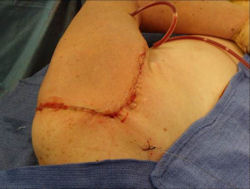

Examples of radical limb sparing surgeries for osteosarcomas in various anatomic locations (distal femur, proximal tibia, proximal humerus, scapula)

In each case, the tumor and bone from which it arose were resected. This required meticulous dissection, mobilization and preservation of adjacent pertinent neurovascular structures. In each case presented here, the defect was reconstructed with a special modular segmental tumor prosthesis. This also replaces the adjacent joint in many instances.

Limb-sparing surgery for osteosarcoma of distal femur – Intraoperative photos

Intraoperative photos